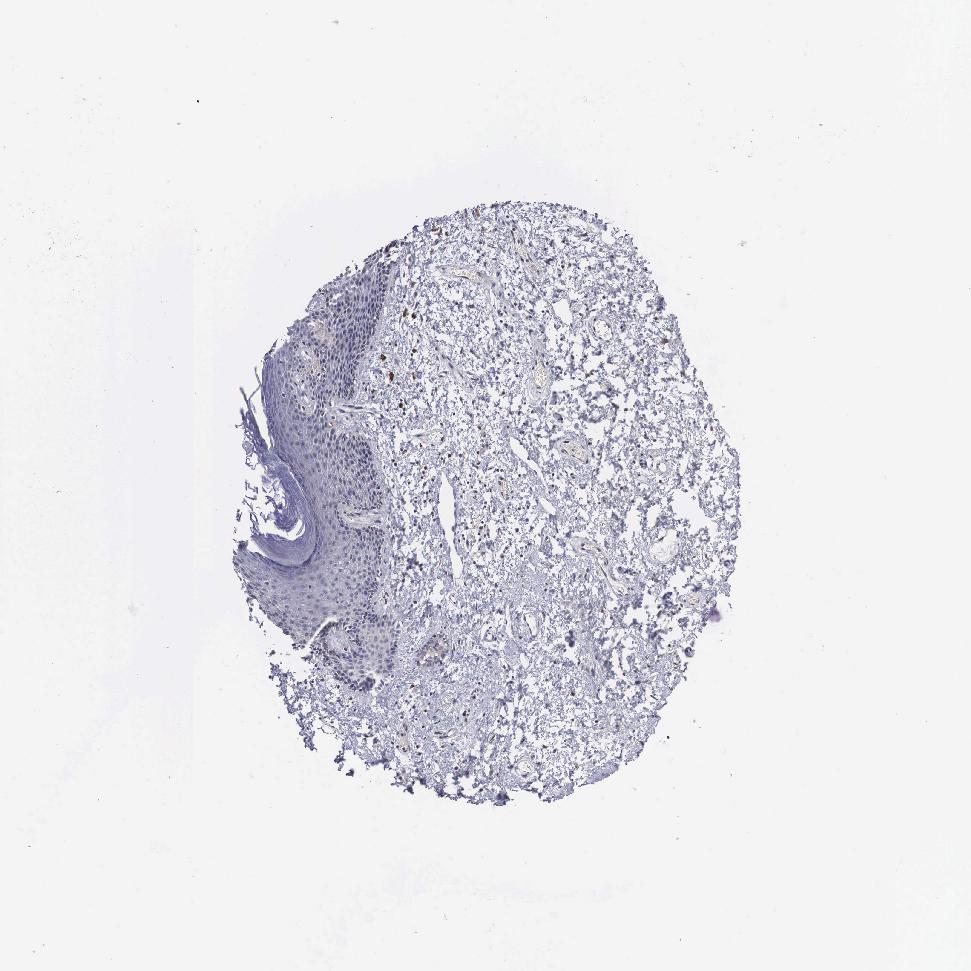

SKIN 1 - Antibody stainingi

Antibody staining in the annotated cell types in the current human tissue is reported as not detected, low, medium, or high, based on conventional immunohistochemistry profiling in selected tissues. This score is based on the combination of the staining intensity and fraction of stained cells.

Each image is clickable and will lead to virtual microscopy that enables deeper exploration of all samples and also displays staining intensity scores, fraction scores and subcellular localization as well as patient and tissue information for each sample.

Antibody HPA000603Antibody CAB025604

Langerhans Not detectedLow

Fibroblasts Not detectedMedium

Keratinocytes Not detectedLow

Melanocytes Not detectedLow